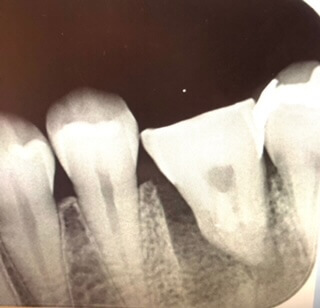

術直後のレントゲン写真です。既存の骨と移植歯との間に大きな隙間があります。

根管治療も終わり、生着が確認できたので歯冠修復(被せ物の装着)を終え、その1年半後のレントゲン写真です。既存の骨と歯との間にあった隙間も骨で満たされているのが分かると思います。